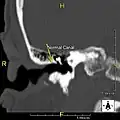

Normal ear canal

-

Exostosis in ear canal

The normal ear canal is approximately 7 mm in diameter and has a volume of approximately 0.8 ml (approximately one-sixth of a teaspoon).[5] As the condition progresses, the diameter narrows and can even close completely if untreated, although people generally seek help once the passage has constricted to 0.5–2 mm due to the noticeable hearing impairment. While not necessarily harmful in and of itself, constriction of the ear canal from these growths can trap debris, leading to painful and difficult to treat infections.